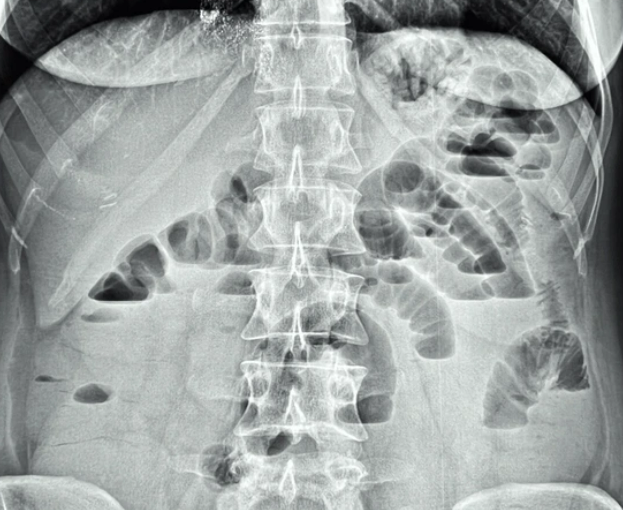

말 그대로 장이 마비되어 장 안의 음식물과 가스, 소화액 등이 제대로 움직이지 못하고 정체되는 상태를 말해요.

보통 우리가 알고 있는 ‘장폐색’은 **물리적으로 막히는 경우(기계적 장폐색)가 많은데,

마비성 장폐색은 장이 움직이지 않아서 생기는 문제예요.

즉, 막힌 것이 아니라 장의 운동이 멈춘 것이죠.